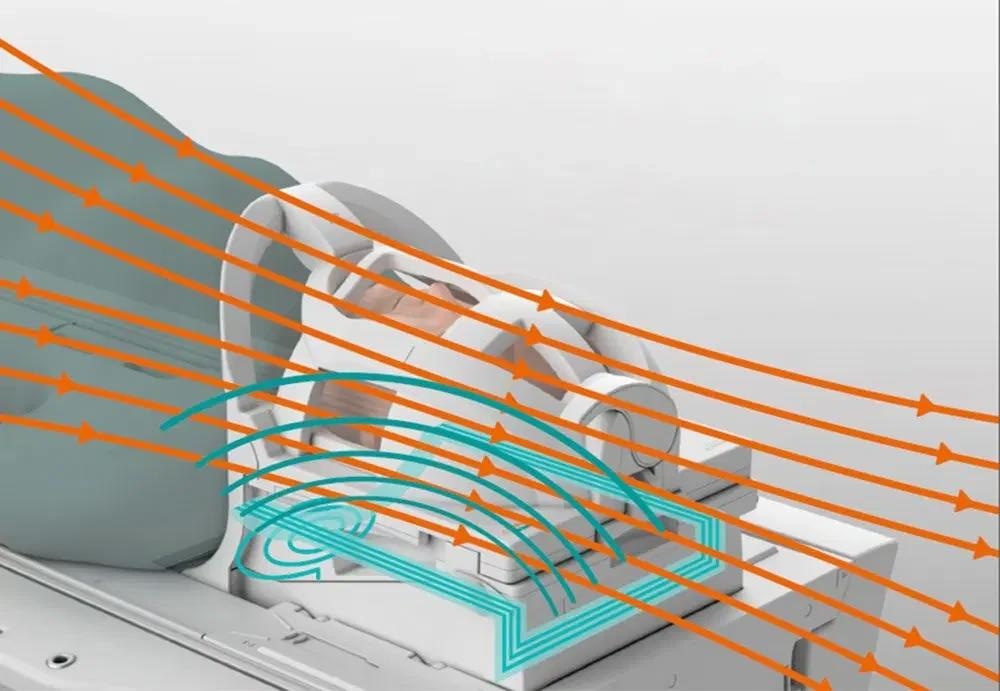

BioMatrix Sensors. New ultra-high density BioMatrix coils utilize seamlessly integrated respiratory sensors to acquire and display the patient’s respiration. Image Credit: Siemens Healthineers.

BioMatrix Tuners. CoilShim and SliceAdjust locally adapt to specific patient anatomy and thereby deliver excellent image quality, fat saturation and homogeneity. Image Credit: Siemens Healthineers.

BioMatrix Sensors — Anticipate motion for high-quality results

BioMatrix Sensors, fully incorporated into the system architecture, capture respiratory and cardiac3 motion, improving consistency and freeing up the user to choose the optimal exam approach. This pairing guarantee high-quality outcomes.

BioMatrix Tuners with CoilShim and SliceAdjust technology

Patient anatomy has physical implications in MRI, like distortion of field homogeneity, which leads to poor image quality.

BioMatrix Tuners use CoilShim and SliceAdjust technology to adjust to difficult anatomical locations, resulting in resilience and reproducible, high-quality imaging for all patients.

As a result of the dramatically improved fat saturation and DWI quality in the head/neck area, CoilShim technology helps prevent repeat scans.

SliceAdjust produces high-quality DWI images, avoiding broken spine artifacts and delivering great correlation to anatomical scans. SliceAdjust also improves fat saturation quality over the full imaging volume in multi-concat TSE exams.